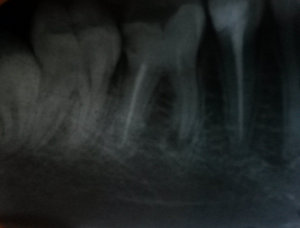

• Да, у верхушки корня зуба есть воспаление. Лекарство надо было ставить до тех пор, пока на рентгенограмме не исчезло бы воспаление, и не восстановилась костная ткань. Скорее всего, вам рано поставили постоянный пломбировочный материал, и инфекция в зубе ещё осталась. Обратитесь к своему лечащему врачу-стоматологу. Постоянный приём обезболивающих препаратов плохо влияет на жел читать далее